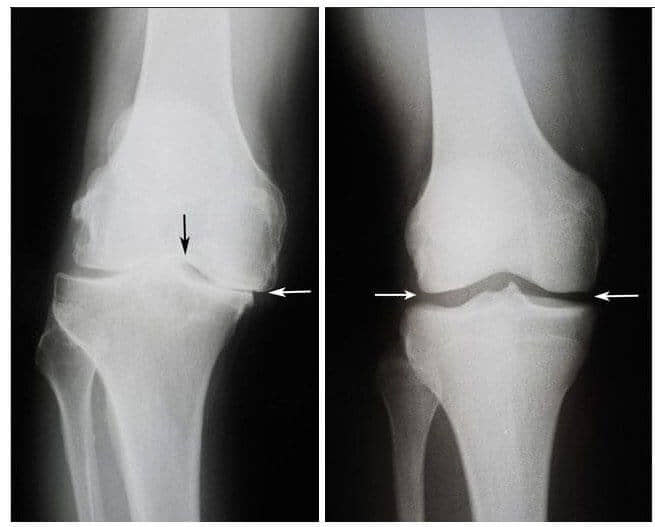

Na levi strani: Rentgenska slika desnega kolenskega sklepa, ga. Violeta, 75 let. Tkivo hrustanca je skoraj povsem uničeno. Zdravniki so ji takrat svetovali vsaditev umetnih sklepov.

Na desni strani: Rentgenska slika desnega kolenskega sklepa, ga. Violeta, po zdravljenju z mazilom Motion Free .